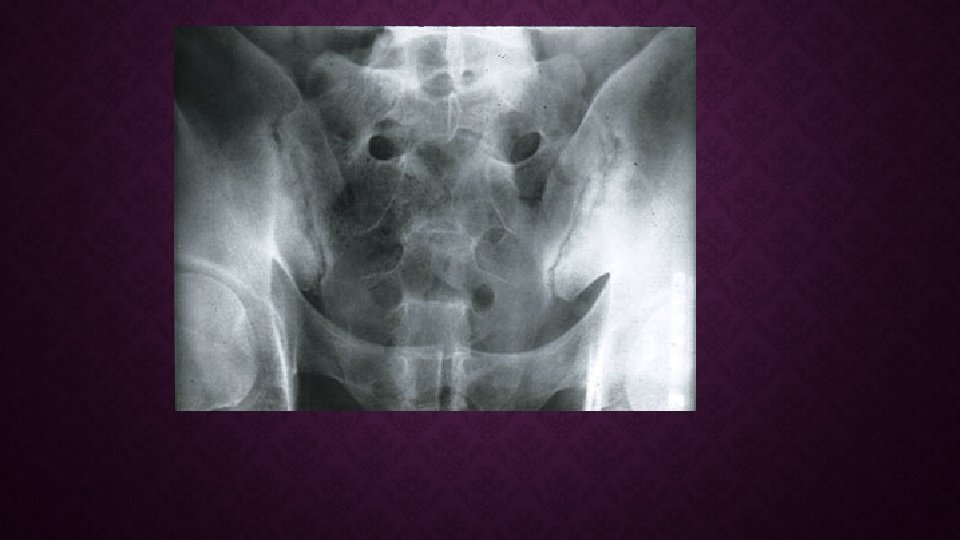

ASP İÇİN MODİFİYE NEW YORK KRİTERLERİ (1984) RADYOLOJİK DİREKT SİE GR. de 2 TARAFLI GRADE 2 Sİİ DİREKT SİE GR. de TEK TARAFLI GRADE 3 -4 Sİİ KESİN ANKİLOZAN SPONDİLİT İÇİN; RADYOLOJİK BULGU ve HERHANGİ BİR KLİNİK KRİTERİN BULUNMASI, KLİNİK İNFLAMATUVAR BEL AĞRISI LOMBER OMURGANIN SAGİTAL VE FRONTAL HAREKETLERİN DE KISITLANMA GÖĞÜS EKSPANSİYONU NUN KISITLANMASI OLASI ANKİLOZAN SPONDİLİT İÇİN; ÜÇ KLİNİK KRİTER VARLIĞI VEYA RADYOLOJİK KRİTERLERİN KLİNİK KRİTERLER OLMADAN BULUNMASI GEREKİR.

SEKEL BULGULA R SİE DİREKT X RAY SENSİTİVİTESİ %10 İLİAK VE SAKRAK KANATLARDA SKLEROZYON/KENAR DÜZENSİZLİĞİ FÜZYON SİE BT SİE MR HASTALIK AKTİVİTESİ İLE İLİŞKİLİ BULGULAR YOK SENSİTİVİTESİ %95 AKTİF İNFLAMASYONU GÖSTERİR HASTALIĞIN TAKİBİNDE KULLANILMAZ SİE SC. SENSİTİVİTESİ %48

VERTEBRANIN X RAY GÖRÜNTÜSÜ COR. VERTEBRALARDAKİ PERİOSTİTE BAĞLI KARELEŞME COR. VERTEBRALARIN KENARINDA, ETRAFI SKLEROTİK EROZYONLAR SİNDESMOFİTLERE BAĞLI BAMBU KAMIŞI VERTEBRA